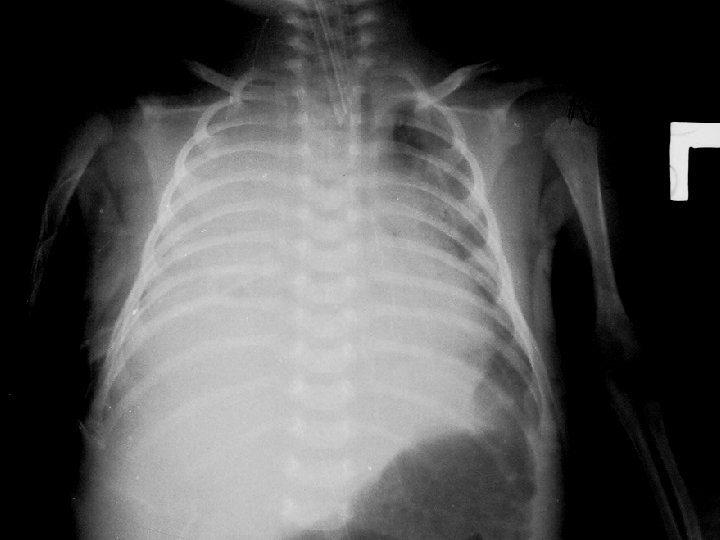

• CBC: Hb= 10, Hct= 31%, WBC= 51, 730/mm 3(N 51, L 34), Plt= 944, 000 , • CXR ��consolidation with right pleural effusion • pleural tapping ��� frank pus ���� Cefotaxime (100 MKD) ������� Amikin (15 MKD) ������������������ (ICD) ��������������������� endotracheal tube �������

• Lungs : decreased breath sound , right dullness on percussion , on ICD at right 5 th intercostal space • Abdomen : soft , liver and spleen can’t be palpable • Extremities : no pitting edema

Film at vajira hospital